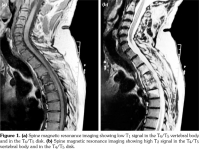

Laboratory examination revealed a slightly elevated C-reactive protein level (16 mg/L) and erythrocyte sedimentation rate (40 mm). Serum levels of calcium, albumin and phosphorus were within the normal range. Blood cell counts, liver tests, and renal function were unremarkable. Blood cultures, urinanalysis, tumor markers, and serodiagnosis for brucella were negative. Tuberculosis skin test was negative. Spine magnetic resonance imaging showed low T1, high T2 signal and contrast enhancement in the T4/T5 and L3 vertebral body and in the T4/T5 disk (Figure 1). Sacroiliac joints were normal. Computed tomography-guided biopsy of the T4/T5 disc demonstrated nonspecific inflammation and culture of this specimen was negative. Computed tomography scan of the sternoclavicular joints revealed hyperostosis and erosions involving the sternum as well as medial end of clavicle (Figure 2). Clavicular biopsy showed irregular sclerotic trabeculae. Human leukocyte antigen B27 typing was positive.